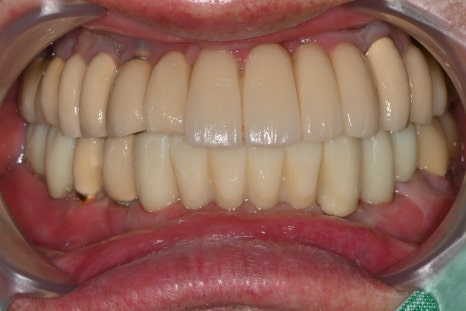

Left photo: Front view of the completed prosthesis. Both esthetics and function were restored satisfactorily.

Right photo: From the side as well, the natural curve and bite were well maintained, allowing comfortable chewing.